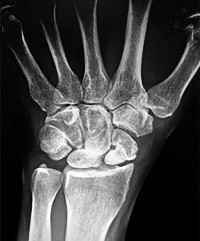

Which of the following describes the correct vascular anatomy and blood supply of the scaphoid, predisposing its proximal pole to avascular necrosis following fracture?

Correct Answer: The primary blood supply enters at the dorsal ridge and supplies the proximal pole via retrograde flow.

Explanation:

The major blood supply to the scaphoid (70-80%) comes from branches of the radial artery that enter the bone via the dorsal ridge (near the waist) and perfuse the proximal pole in a retrograde fashion. Because of this retrograde flow, fractures at the waist or proximal pole can disrupt the blood supply to the proximal fragment, greatly increasing the risk of avascular necrosis and nonunion.